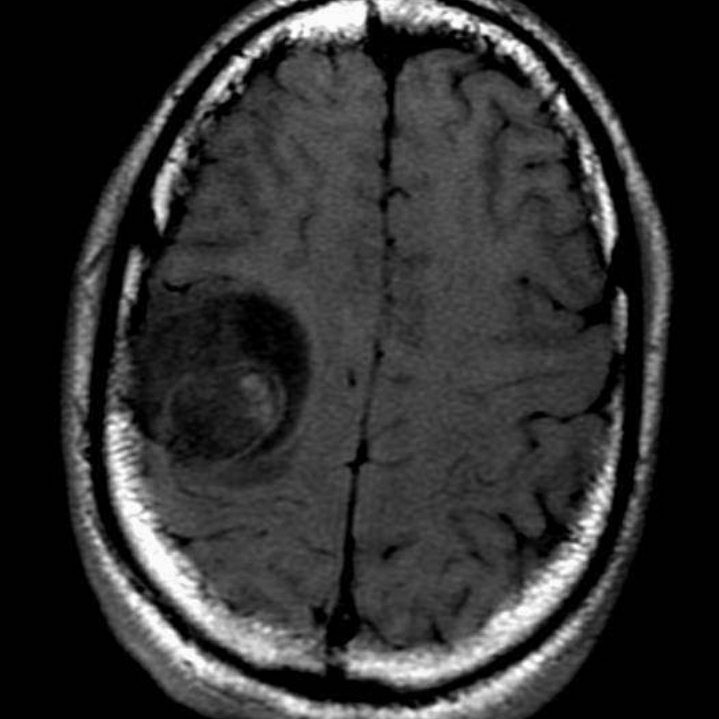

I’m a 17-year glioblastoma brain cancer survivor. I suffered greatly during cancer treatment and If I knew then what I know now, I would have used hemp-based products to find relief from the side effects of radiation and chemotherapy. Cancer patients are increasingly purchasing hemp products but the costs are high. I created the nonprofit so we can overcome that barrier and learn more in the process through case studies.